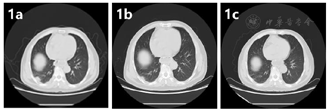

2021年9月11日胸腹平扫+增强CT提示:(1)食管癌治疗后,请结合临床及老片;(2)考虑右肺放疗后改变,右下肺结节较2021年7月22日片明显缩小;右侧胸膜增厚;(3)升主动脉增粗,主动脉及冠状动脉粥样硬化;(4)右肾小囊肿,右肾结石;(5)左肾未见明显显示,左肾上腺结节、腹腔及腹膜后结节、左胸壁皮下结节及肝右叶异常强化影,较前片2021年7月22日片相仿(图1,图2,图3)。